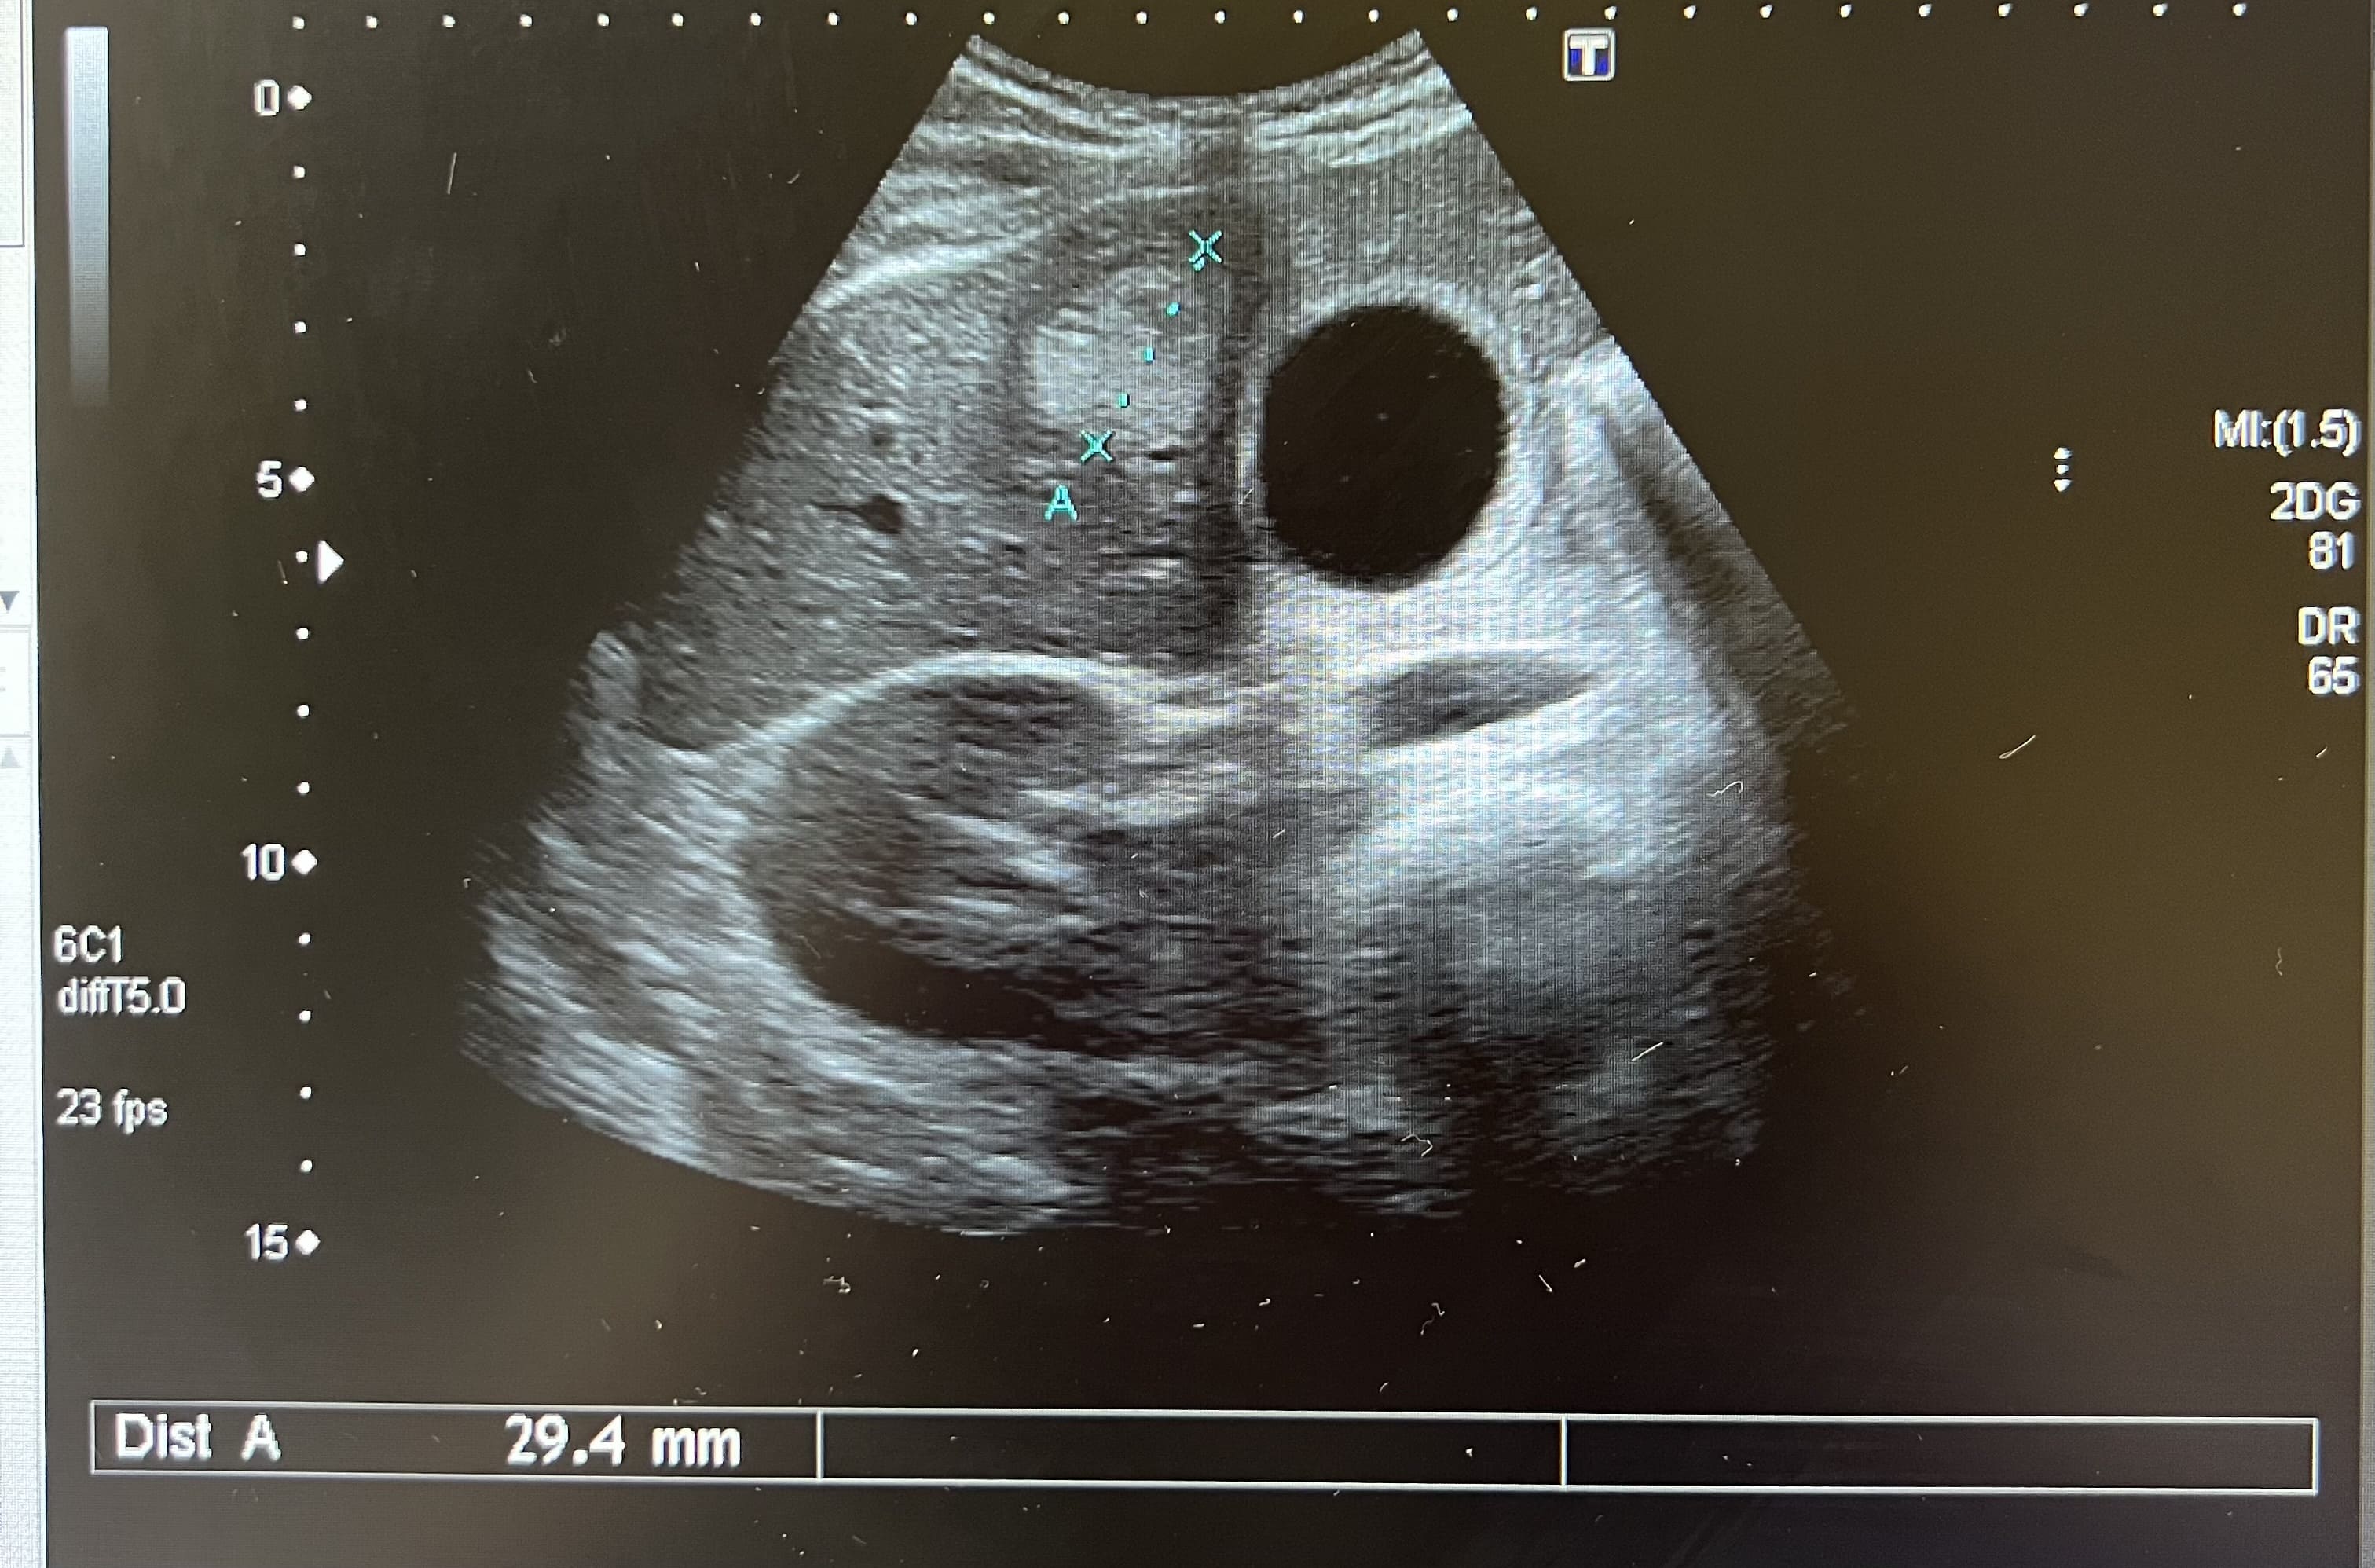

Pruebas complementarias: analítica normal. La ecografía abdominal muestra múltiples imágenes ecogénicas bien definidas en ambos lóbulos, de tamaño variable. Vesícula biliar con dos litiasis subcentimétricas y discreto edema de pared compatible con colecistitis. Estos hallazgos se confirman mediante la realización de una ecografía reglada por parte de radiología.

Juicio clínico: Hemangiomas hepáticos. Colecistitis.

Diagnóstico diferencial: con otras lesiones focales sólidas del hígado. La imagen ecográfica del hemangioma es de una o varias lesiones hiperecogénicas bien definidas que no captan Doppler. La hiperplasia nodular focal se presenta como una lesión hipo o isoecoica que puede captar Doppler. El adenoma se presenta como una masa hiper o hipoecoica con áreas anecoicas, mostrando el Doppler un tumor hipervascular. El hepatocarcinoma tiene un aspecto ecográfico variable, como masa o nódulos hipoecoicos, mal diferenciados e hipervascularizados. Las metástasis hepáticas se suelen presentar como múltiples lesiones sólidas de tamaño y ecogenicidad variables y la presencia de un halo hipoecoico rodeando la masa.

El hemangioma hepático es el tumor hepático benigno más frecuente, con mayor prevalencia en mujeres. Se suelen presentar en forma de lesión única, aunque pueden aparecer en forma de lesiones múltiples, con un tamaño normalmente inferior a 30 milímetros. Suele ser un hallazgo casual, al ser asintomáticos. El diagnóstico diferencial se realiza con otras lesiones hepáticas sólidas y se recomienda un seguimiento ecográfico para confirmar estabilidad.